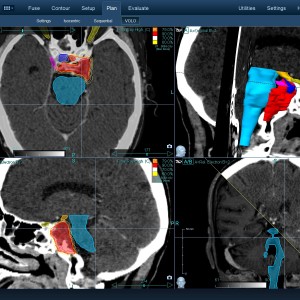

Στις παρακάτω φωτογραφίες θα δείτε παραδείγματα πλάνων θεραπείας καρκινικών όγκων με CyberKnife. Παρατηρήστε πόσο κοντά στους υγιείς ιστούς βρίσκονται οι καρκινικοί όγκοι που χρειάζεται να ακτινοβοληθούν. Μόνο με το CyberKnife και το προσωπικό πλάνο θεραπείας, μπορούν να ακτινοβοληθούν οι όγκοι χωρίς να πληγούν οι παρακείμενοι υγιείς ιστοί.

Με κόκκινο χρώμα περιγράφεται η περιοχή του όγκου.

Με μπλε, κίτρινο και πράσινο χρώμα περιγράφονται οι υγιείς ιστοί που δεν πρέπει να ακτινοβοληθούν.

Παρατηρήστε πόσο κοντά βρίσκεται ο όγκος με τους υγιείς ιστούς.

Παρατηρήστε τις πάρα πολλές δέσμες του CynerKnife που ακτινοβολούν τους όγκους από διαφορετικές γωνίες ώστε να μην προσβληθούν από την ακτινοβολία οι υγιείς ιστούς.